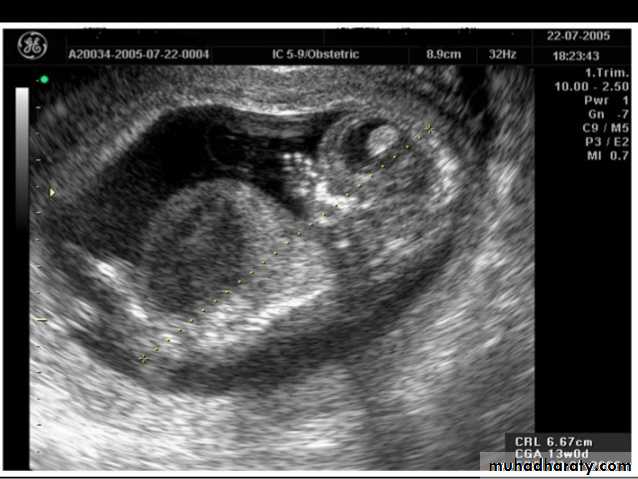

BPD together with head circumference (HC), abdominal circumference (AC), and femur length (FL) are computed to produce an estimate of fetal weight. In the second trimester this may be extrapolated to an estimate of gestational age and an estimated due date (EDD) .